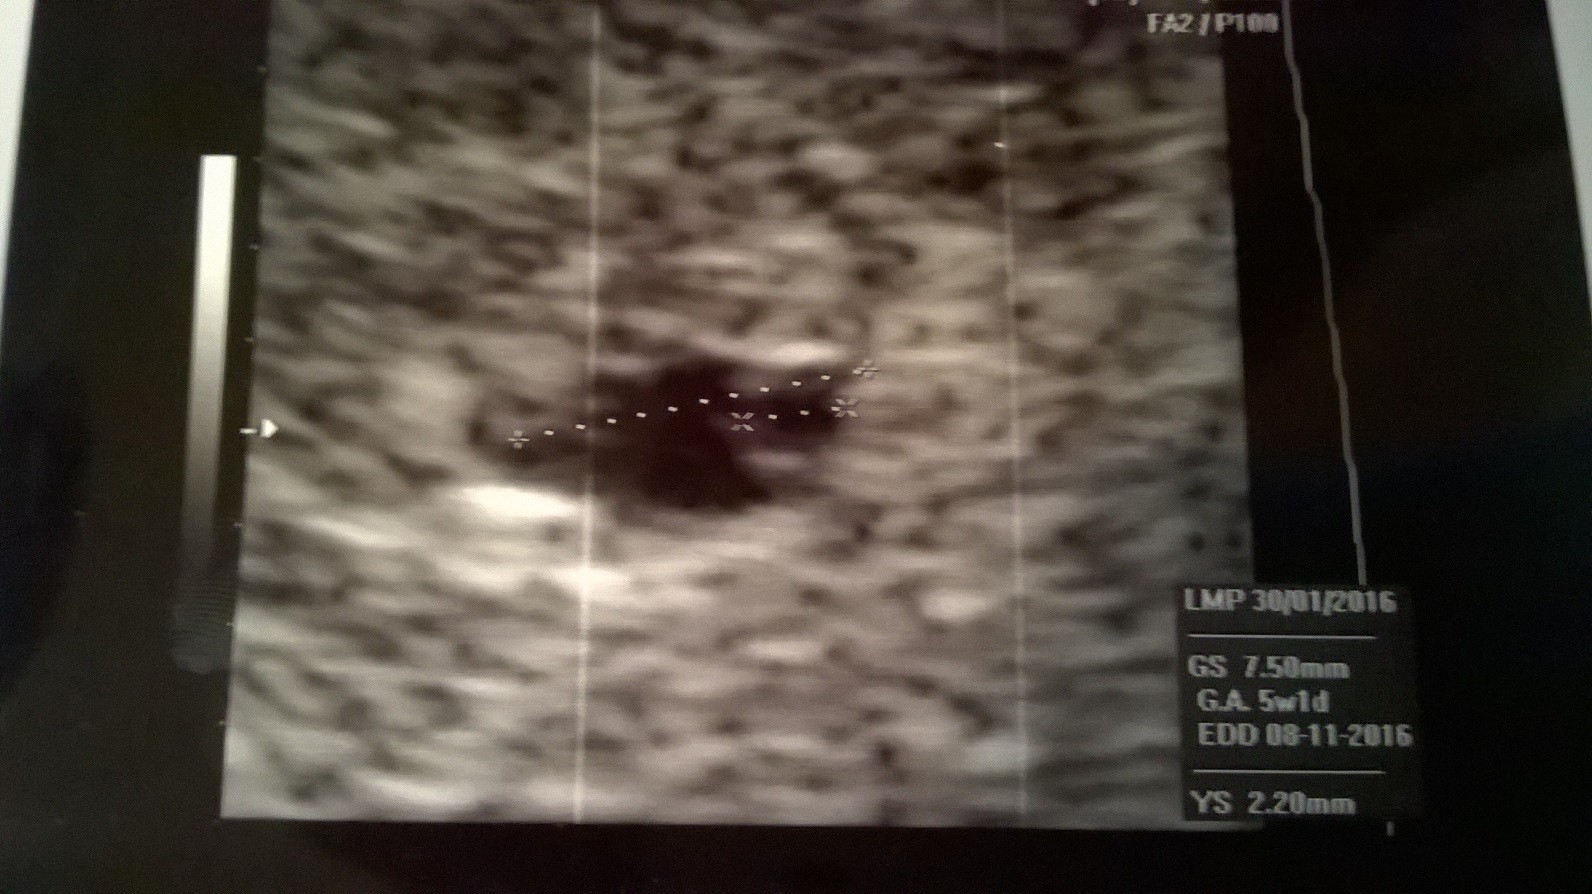

Myślicie że na USG jest wszystko dobrze ?

WP_20160309_001.jpg

• WP_20160309_001.jpg

391,7 KB · Wyświetleń: 229